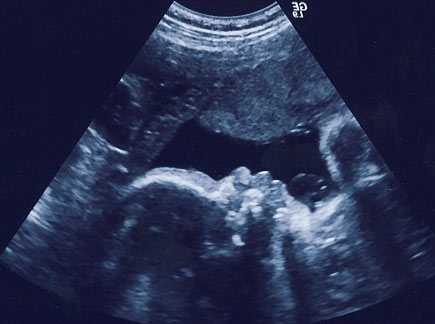

УЗИ

В тридцать недель беременности скрининговое ультразвуковое исследование не проводится. Однако возможно выполнение УЗИ по медицинским показаниям, например, нарушение активности плода, задержка его развития. УЗИ иногда рекомендовано для уточнения срока беременности, при оплодотворении методом ЭКО.

При выполнении УЗИ в трёхмерном, четырёхмерном формате можно детально рассмотреть ребёнка, получит фотографии и видеозапись.

Диагностика пола в тридцать недель беременности может быть осложнена в связи с принятием плодом сгибательной позы. Специалисты выделяют следующие усреднённые нормы фетометрии:

- БПР – до 78 мм;

- длина бедренной кости – до 56 мм;

- длина предплечья – до 46 мм;

- длина костей голени – до 79 мм;

- длина плечевой кости – до 53 мм;

- ЛЗР – до 97 мм;

- диаметр грудной клетки – до 79 мм;

- окружность живота – до 264 мм;

- окружность головы – до 285 мм.

Существенным является определение предлежания плода, количества сосудов, расположенных в пуповине, степени зрелости плаценты. Специалист также тщательно изучает внутренние органы. В тридцать недель беременности можно с высокой точностью выявить пороки развития.